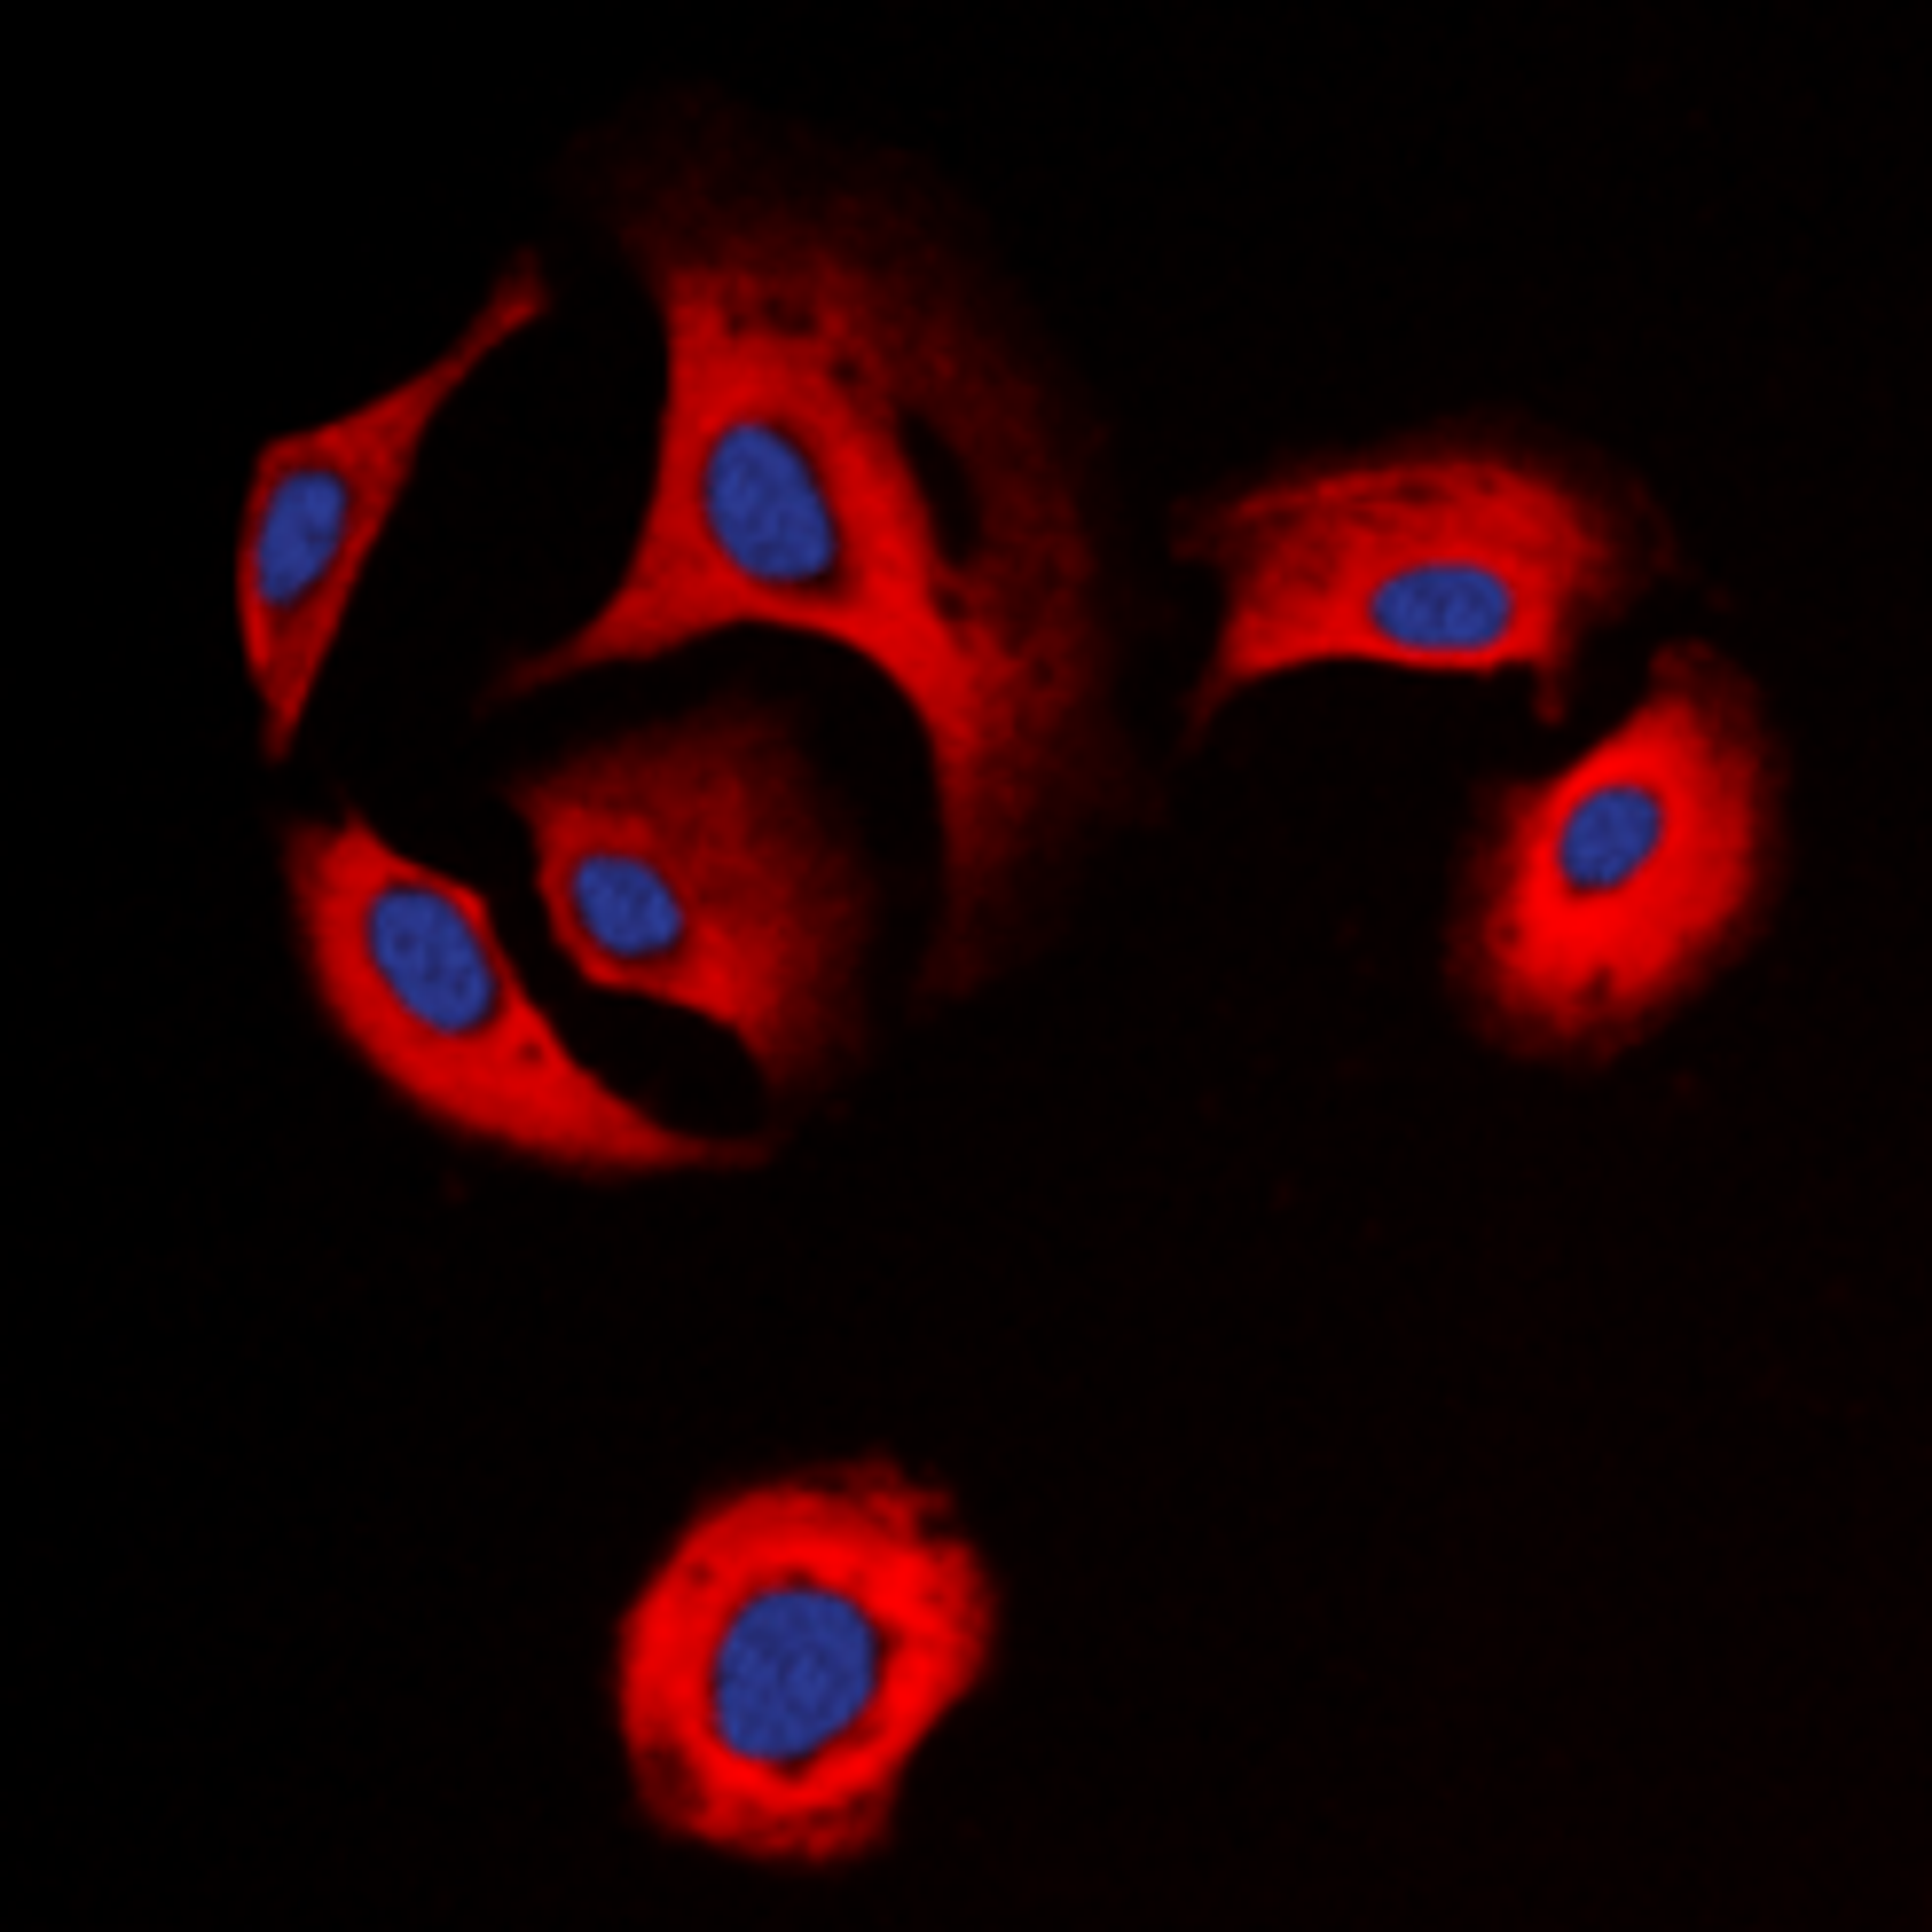

Estrogen Receptor beta antibody

- orb389114

- Host

- Mouse

- Reactivity

- Horse (Equine), Human, Monkey, Pig (Swine), Rat

- Applications

- Flow Cytometry, Immunofluorescence (Paraffin-Embedded Sections), Immunohistochemistry (Paraffin-Embedded Sections), Western Blotting